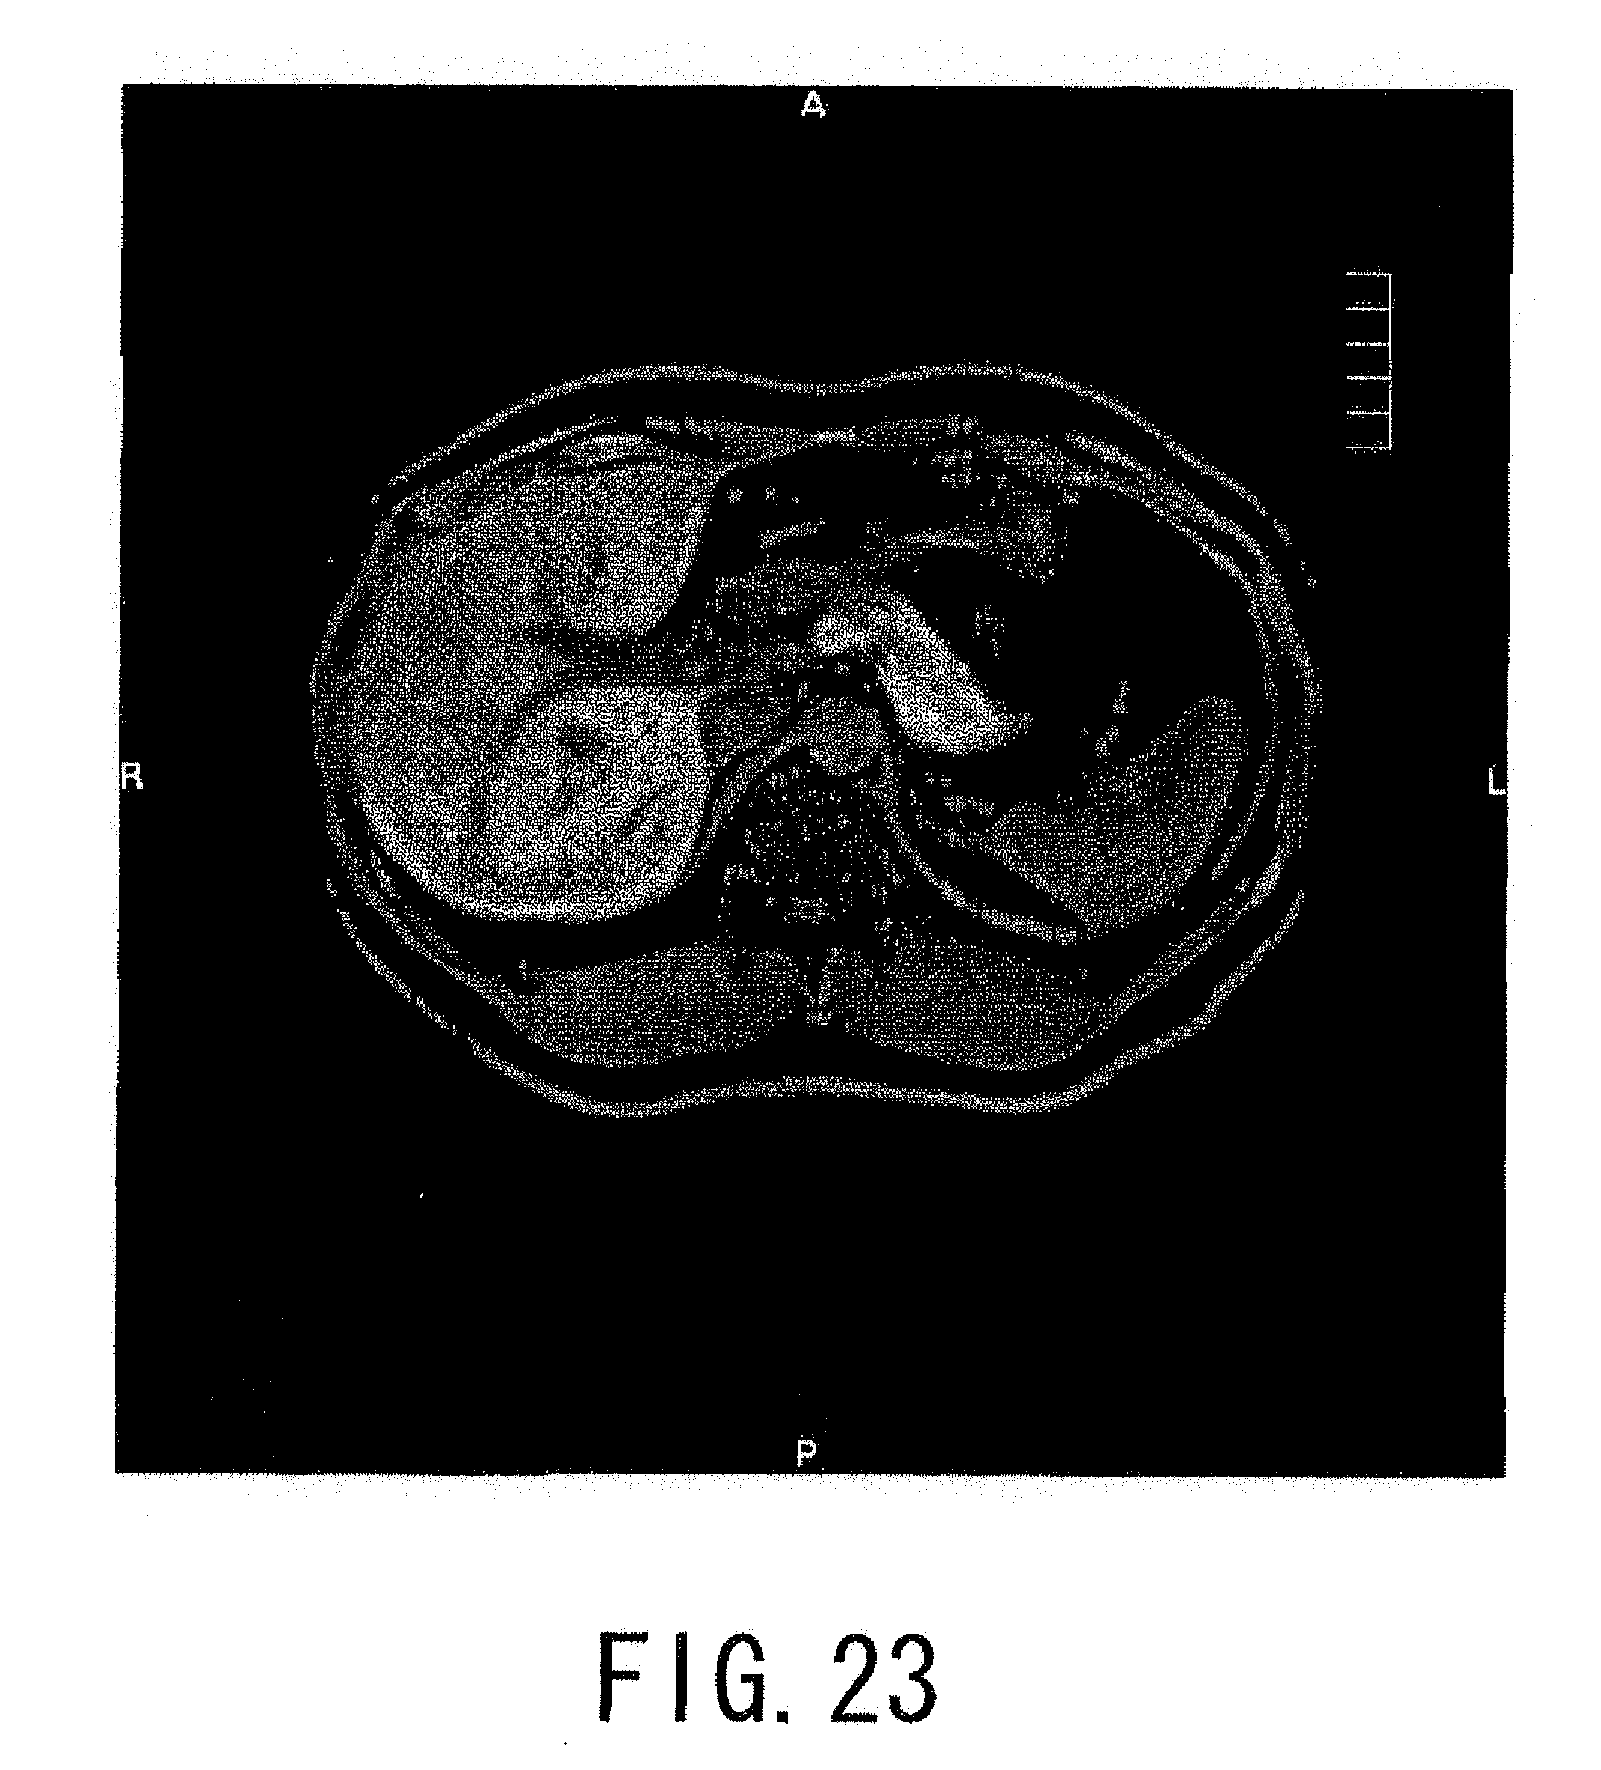

FIG. 23 is a tomographic image of the object obtained with fat-saturation by applying an SPIR pulse and a CHESS pulse of which frequencies are set to a resonance frequency of fat signals with the magnetic resonance imaging apparatus shown in FIG. 9; and

FIG. 23 is a tomographic image of the object P obtained with fat-saturation by applying an SPIR pulse and a CHESS pulse of which frequencies are set to a resonance frequency of fat signals with the magnetic resonance imaging apparatus 20 shown in FIG. 9.

As shown in FIG. 23, it is confirmed to suppress fat satisfactorily by applications of the SPIR pulse and the CHESS pulse.

That is, the magnetic resonant imaging apparatus 20 described above makes fat saturation effect improved by combining plural fat saturations. For example, fat signals in a wider frequency band can be suppressed by an SPIR pulse and remaining fat signals can be suppressed by a CHESS pulse additionally. For example, applying plural CHESS pulses having mutually different frequencies can make fat saturation effect improved in a region, such as a jaw, in which a resonant frequency of fat signals is shifted due to an uneven static magnetic field.